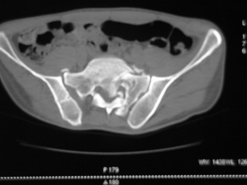

Диагноз : Сочетанная травма. ЗЧМТ. Перелом свода черепа. Ушиб головного мозга.Разрыв лонного и крестцово-подвздошного сочленений с нарушением целостности тазового кольца, с массивной забрюшинной гематомой и пропотеванием в брюшную полость. Перелом 10 ребра справа, осложненный гемопневмотораксом справа, правосторонней пневмонией на фоне ушиба правого легкого. Шок 3-4 ст. Больной поступил в отделение 07.03.2005г. в 16.00 в экстренном порядке через 30 минут после автодорожной травмы.Доставлен КСП. При поступлении состояние больного крайне тяжелое, явления травматического шока, А/Д-80/60 мм.рт. ст. ЧСС-120.В экстренном порядке поднят в операционную, интубирован, совместно с диагностическими мероприятиями лечение шока.При осмотре выявлены перелом 10 ребра справа, разрыв лонного и правого крестцово-подвздошного сочленений. Имеется линейный перелом теменной и височной костей слева с переходом на основание. Диагностическая лапароскопия 07.03.2005г. в 16.30-массивная забрюшинная гематома малого таза.Оставлена контрольная, дренажная трубка.Учитывая кровь в моче произведена цистография - данных за разрыв мочевого пузыря не найдено. Больной переведен в реанимационное отделение.За 08.03.2005г. из брюшной полости выделилось до 1500,0 мл, крови, часть крови реинфузирована. 08.03. в 06.30 наложен торокоцентез справа,удалено 100,0 мл. крови и 200,0 мл. воздуха .. Учитывая продолжающеееся кровотечение в брюшную полость из перелома костей таза, для исключения возможного разрыва внутренних органов 09.03.2005г. произведена Видеолапароскопия., на которой повреждения органов брюшной полости не выявлено.Одновременно произведен шов лонного сочленения проволокой и винтами, с одномоментным наложением стержневого аппарата на кости таза, с целью уменьшения кровотечения из разрывов тазовых сочленений, дренирование гематом. В последующем состояние больного оставалось тяжелым. 10.03.наложена нижняя трахеостома.Далее неоднократно производилась лечебно-диагностическая ФБС.С 10.03 выявлена правосторонняя плевропневмония. КТ головного мозга от 10.03-субарахноидальноекровоизлияние.Срединные структуры не смещены. КТ-контроль от 15.03-открытая моновентрикулярная гидроцефалия4 желудочка. Полисинусит. Постепенно состояние больного медленно прогрессировало к улучшению.С 24.03 переведен на самостоятельное дыхание, а 09.03 переведен в травматологическое отделение.Аппарат стержневой снят из-за перелома стержня (раскрутил больной самостоятельно).После госпитализации в наше отделение проведено дополнительное обследование Рентгекнография, КТ.Хотелось бы услышать Ваше мнение о дальнейшей тактике.-- С уважением, Leonid

Углядел билатеральное повреждение таза. Имеется вертикальная нестабильность со стороны перелома боковой массы крестца, ротационная с контрлатеральной стороны - чрезподвздошный разрыв кп сочленения. Разрыв лона, запирательные отверстия вроде целы.

DS. на сегодняшний день: Вертикальная двусторонняя нестабильная деформация таза, неправильно срастающийся перелом боковой массы крестца слева, срастающийся перелом крыла правой подвздошной кости, застарелый частичный разрыв правого кп сочленения, застарелый разрыв лонного сочленения.

План жизни - оперативное лечение. ЧКО таза (кольцевая опора), последовательная фиксация задних отделов с низведением перелома крестца, синтез лона пластинами, илиосакральное блокирование.

Следует заметить, что подобное привинчивание проволокой лонных костей редко приносит удовлетворение и то только при ротационно-нестабильных повреждениях от бовового сжатия без "ручки корзины". Разрушение заднего комплекса делает неэффективным любую фиксацию передних отделов. Надо обезательно хватать задние отделы.